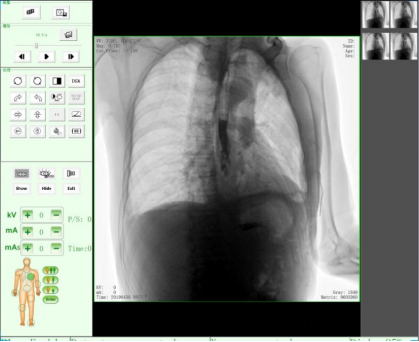

隨著人們健康意識(shí)不斷提高,越來越多人重視健康體檢,而數(shù)字化DR拍片幾乎是體檢必檢項(xiàng)目之一,胸片結(jié)果正常DR報(bào)告顯示為:胸廓對稱,兩側(cè)肋骨、肋間隙正常;兩肺紋理清晰,未見明顯實(shí)質(zhì)性浸潤;兩側(cè)肺門和縱隔影來見明顯異常;心臟大小、形態(tài)在正常范圍內(nèi);膈肌平滑,雙側(cè)肋膈角銳利時(shí),則說明您一切正常。那么,數(shù)字化DR胸片報(bào)告不正常的結(jié)果有哪些呢?

3、兩肺紋理增粗、紊亂,呈網(wǎng)狀或條索狀、斑點(diǎn)狀陰影。

老慢支,肺氣腫,肺心病,這時(shí)您的數(shù)字化DR片可能會(huì)呈現(xiàn)這種胸片,當(dāng)進(jìn)一步發(fā)展時(shí),將會(huì)出現(xiàn)兩肺透亮度增加。由于肺泡過度通氣致使X光胸片上黑化度增加,即越黑透亮度越大。哮喘發(fā)作時(shí)同樣可見兩肺透亮度增加,呈過度充氣狀態(tài)。當(dāng)然,X線攝影條件過高或是顯影時(shí)間過長也會(huì)導(dǎo)致這樣。

如果臨床表現(xiàn)為在原有咳嗽、咳痰的基礎(chǔ)上有逐漸加重的呼吸困難,甚至有胸悶、氣急、桶狀胸。常見的嚴(yán)重肺氣腫、肺大泡還會(huì)導(dǎo)致氣胸,也就是胸腔內(nèi)的氣體將肺壓縮,使被壓縮的肺與胸壁間出現(xiàn)透明的含氣區(qū),其中不見肺紋理。這些多是由白變黑的異常。